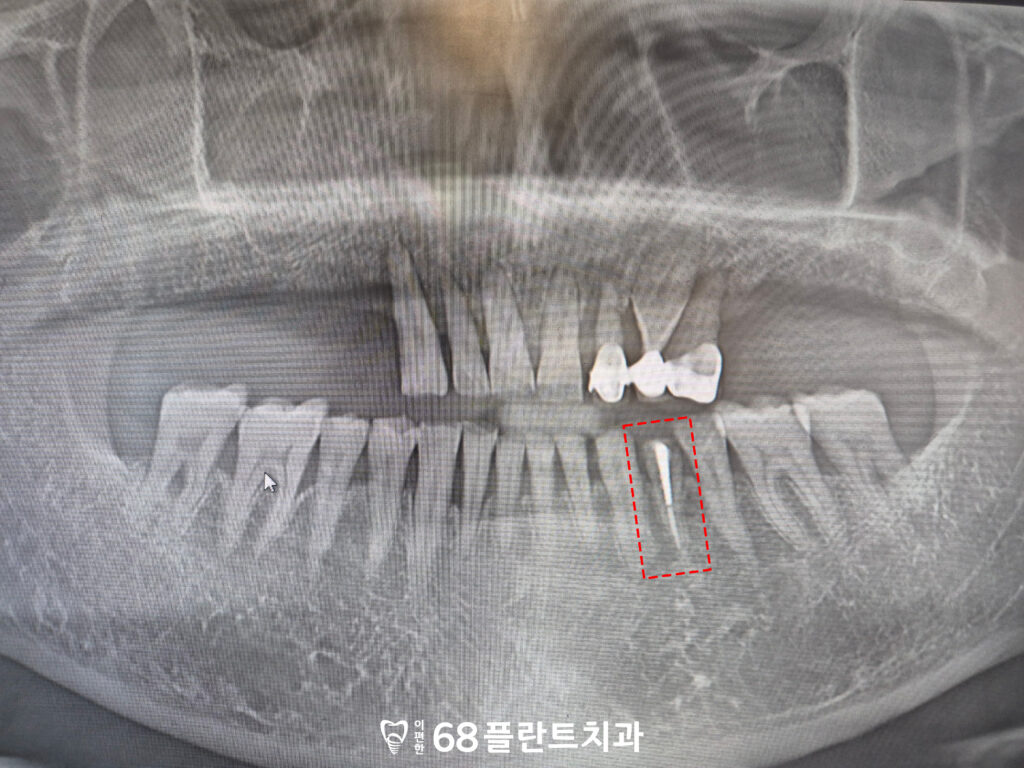

마지막으로 왼쪽 아래 치아는

오래 전 신경치료를 받은 이후,

위 보철을 씌우지 않고

치료를 중단한 상태였으며

그로 인해 치관부가

파절된 모습이 확인되었습니다.

신경치료를 받은 치아는 내부 수분이 감소해

상대적으로 취약해질 수 있는데,

보철 수복 없이 장기간 사용하게 되면

저작 압력에 의해 균열이나

파절이 발생할 가능성이 높습니다.

그래서 해당 치아도

발치 후 임플란트를 식립하기로 하였으며

전체적인 치료 계획을 전부 수립하였습니다.